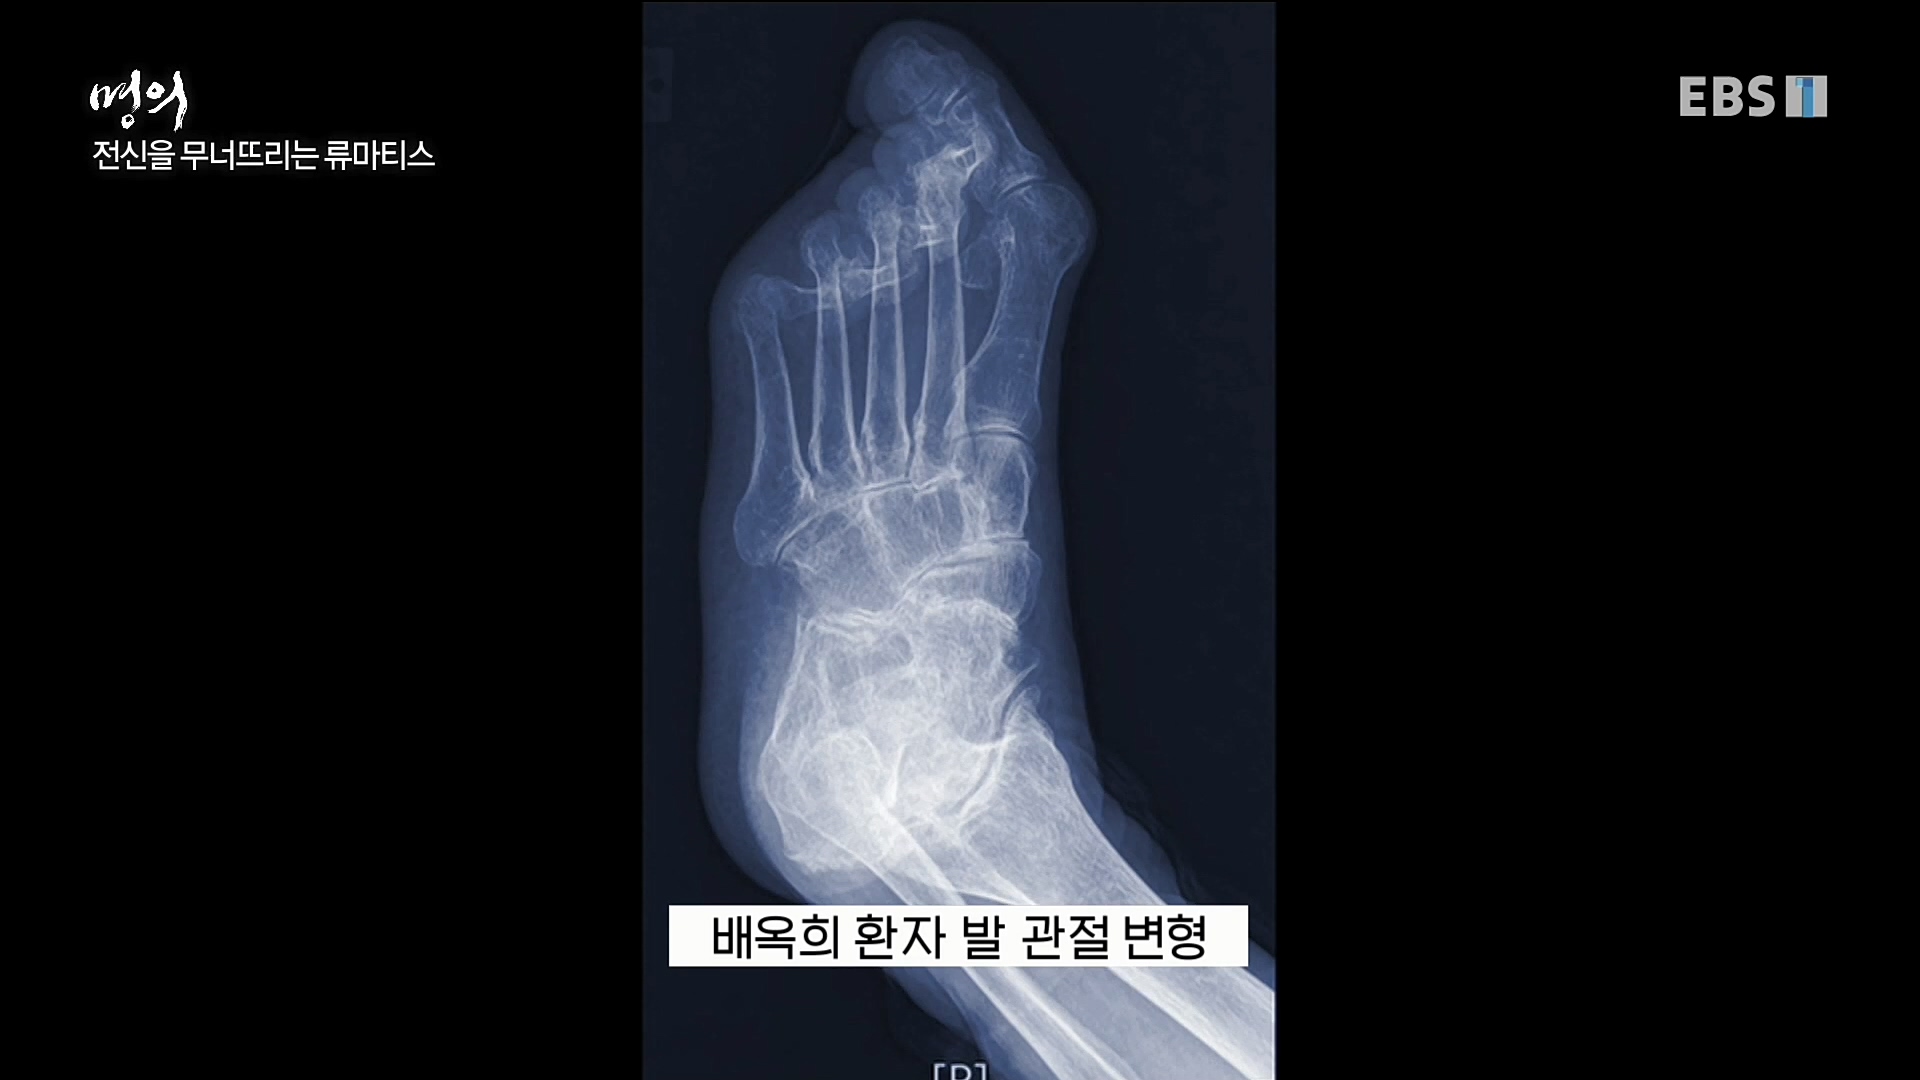

'명의' 이연아 교수가 전하는 류마티스 관절염의 원인 및 치료법 방송을 보고나서..

류마티스 관절염은 관절을 싸고 있는 얇은 막인 '활막'에 지속적인 염증 반응이 나타나는 만성 염증성 전신 질환이자 자가 면역 질환이다. 면역 체계의 ...